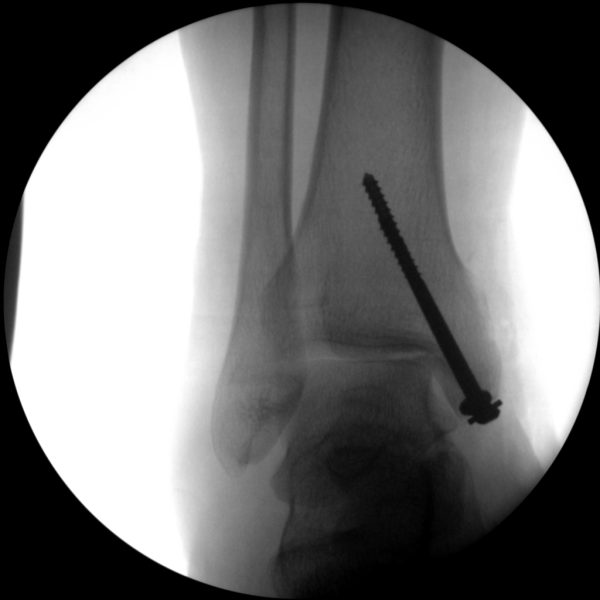

Skan-C plays a critical role in orthopaedic procedures, providing excellent imaging during interventional procedures, and allowing for precise localization and accurate treatment. The ability of Skan-C to offer dynamic visualization of visualization structures enhances patient safety, minimizes complications, and improves the overall effectiveness of orthopedic interventions.

CRIF - Closed reduction internal fixation

ORIF - Open reduction internal fixation

Clinical Evidence

Skan-C is a great C-arm for orthopaedic treatments for several reasons